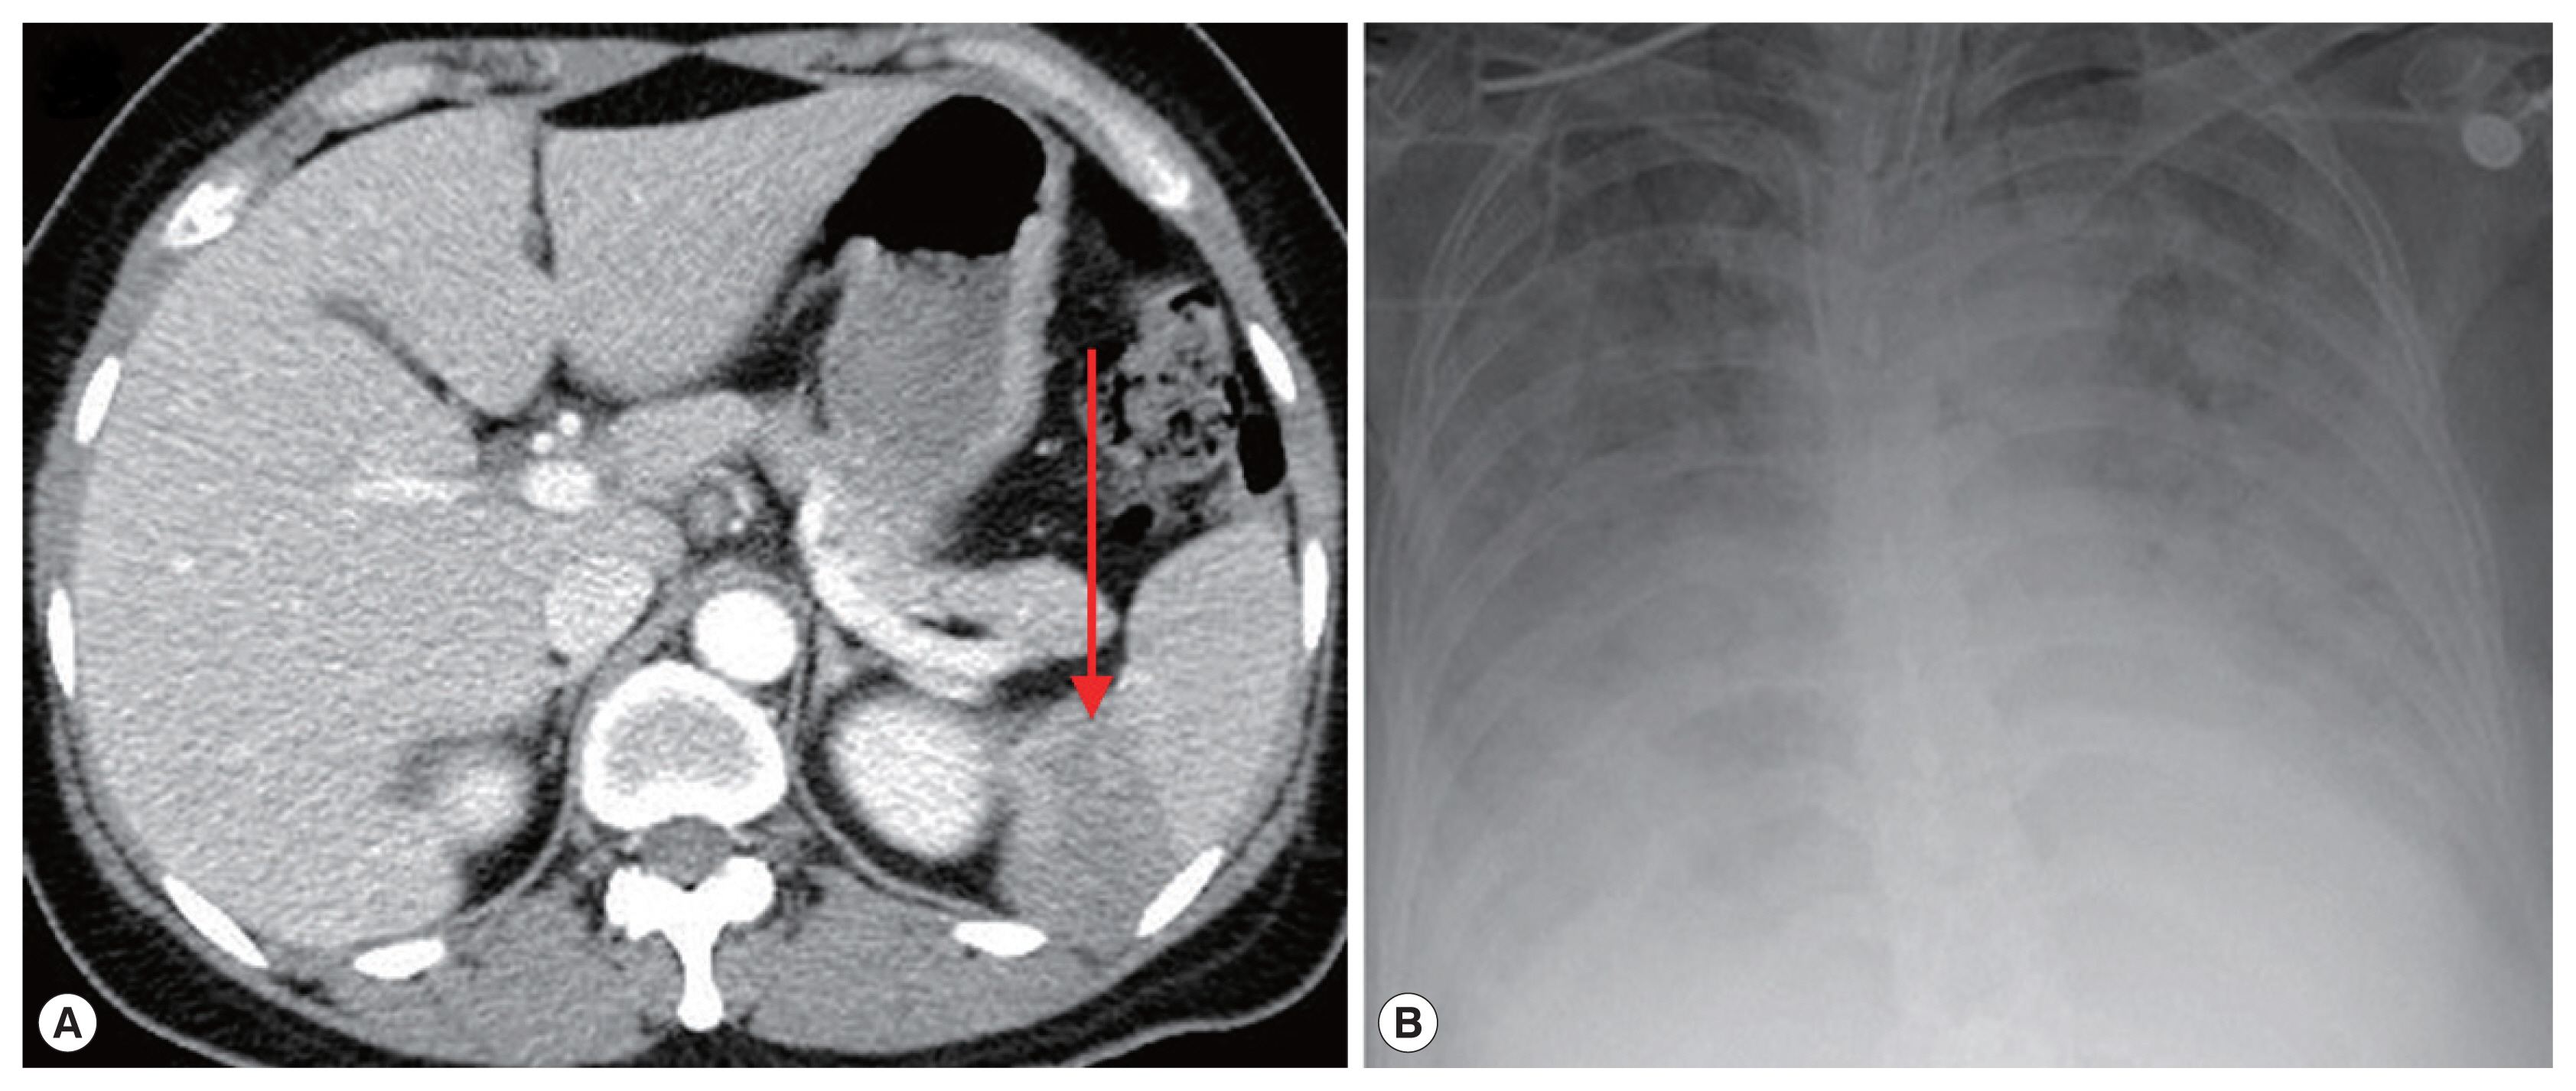

On admission, her vital signs were: blood pressure 148/73 mmHg, heart rate 120 beats per minute, respiratory rate 18 breaths per minute, and body temperature 40.7°C. Laboratory examination showed white blood cells 5,610 cells/μl (normal range 4,000–10,000 cells/μl), hemoglobin 11.2 g/dl (normal range 12.0–15.3 g/dl), platelets 53,000 cells/μl (normal range 150,000–400,000 cells/μl), erythrocyte sedimentation rate 69 mm/hr (normal range 1–22 mm/hr), and C-reactive protein 9.52 mg/dl (normal range 0.0–0.3 mg/dl). Blood smear showed erythrocyte-containing organisms suspicious for Plasmodium species (Fig. 1). Abdomen-pelvis computed tomography revealed findings consistent with splenic infarction.

Suspecting malaria complicated with splenic infarction, treatment with hydroxychloroquine (800 mg loading and 400 mg 3 times after 6, 24, and 48 hr) was initiated. However, tests for detecting malaria antigens and polymerase chain reaction (PCR) for Plasmodium species failed to confirm malaria [16]. When the blood smear slide was re-examined, 4 Plasmodium-like organisms in 1 erythrocyte emulating Maltese cross forms were observed (Fig. 2A). We prescribed atovaquone 250 mg/proguanil hydrochloride 100 mg and azithromycin 500 mg to treat babesiosis. PCR for B. microti confirmed the diagnosis of babesiosis. A day after treatment, fever and abdominal discomfort subsided, and laboratory findings returned to normal.

A 72-year-old woman without underlying disease visited our hospital for a fever that started 2 weeks before. She had been in Boston in the United States for 2 months previously. Vital signs were: blood pressure 93/67 mmHg, heart rate 76 beats per minute, respiratory rate 18 breaths per minute, and body temperature 37.7°C. Laboratory findings showed white blood cells 5,480 cells/μl, hemoglobin 10.8 g/dl, platelets 52,000 cells/μl, erythrocyte sedimentation rate 105 mm/hr, and C-reactive protein 15.1 mg/dl. Malaria-like organisms were seen on the observation of blood smear; however, the malaria antigen test was negative. When the blood smear morphology was closely observed, Maltese cross forms were visible in the red blood cells; therefore, babesiosis was diagnosed (Fig. 1B). Atovaquone 250 mg/proguanil 100 mg and azithromycin 500 mg were prescribed. However, fever persisted, and she developed pulmonary congestion. On diagnosis of severe babesiosis, we switched the medication to quinine and clindamycin, and red blood cell exchange was performed. As pulmonary congestion exacerbated, she was intubated due to respiratory failure (Fig. 2B). Doxycycline therapy was prescribed for possible coinfection with Borrelia or Anaplasma species.